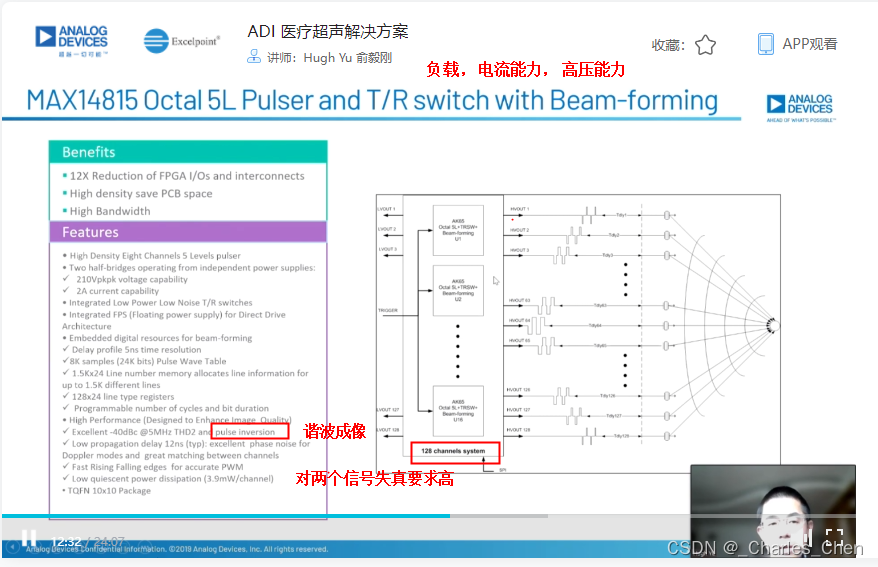

数字发射波束成形器用于产生所要求的数字发射信号,以正确的时间和相位生成聚焦发射信号。高性能超声系统可通过任意波形发生器产生复杂的发射波形,从而优化图像质量。这些情况下,发射波束成形器以大约40MHz速率生成8位至10位数字字符,并以此产生所要求的发射波形。数/模转换器(DAC)将数字波形转换成模拟信号,通过线性高压放大器进行放大,用于驱动传感器单元。由于这种发射技术占用较大体积,而且价格昂贵、需要消耗较高能量,所以,这种架构只限于昂贵的非便携设备。多数超声系统并不使用这种发射波束成形技术,而是采用多级高压脉冲发生器产生需要发射的信号。在这种替代方案中,利用高集成度、高压脉冲发生器快速切换传感器单元至适当的可编程高压电源,产生发射波形。为了产生一个简单的两极发射波形,脉冲发生器需要交替地将传感器单元切换到由数字波束成形器控制的正、负发射电压。更复杂的设计可以让传感器单元切换至多路电源和地,从而产生更复杂、性能更好的多重波形。

近几年,随着二次谐波成像的广泛应用,高压脉冲发生器对于斜率和对称性的要求越来越高。二次谐波成像利用了人体的非线性声学特性。这些非线性特性倾向于将频率fo的声能转变成2fo频率。多种原因使得接收二次谐波信号能够获得更高的图像质量,因此,二次谐波成像得到了广泛应用。

二次谐波成像有两种基本的实现方法。一种称为标准谐波成像,尽可能抑制发射信号的二次谐波,从而使接收到的二次谐波主要源于人体的非线性。这种模式要求二次谐波的发射能量至少低于基波能量50dB。所以,发射脉冲的占空比要求是准确的50%且误差小于±0.2%。另一种方法称为脉冲反相,利用反相后的发射脉冲产生同一图像路径的相位相反的两路接收信号。在接收器中对这两路反相接收信号求和,恢复由于人体非线性产生的谐波信号。这种脉冲反相的方法必须在叠加时尽可能抵消发射脉冲的反相成分。所以,高压脉冲发生器的上升时间和下降时间必须严格一致。